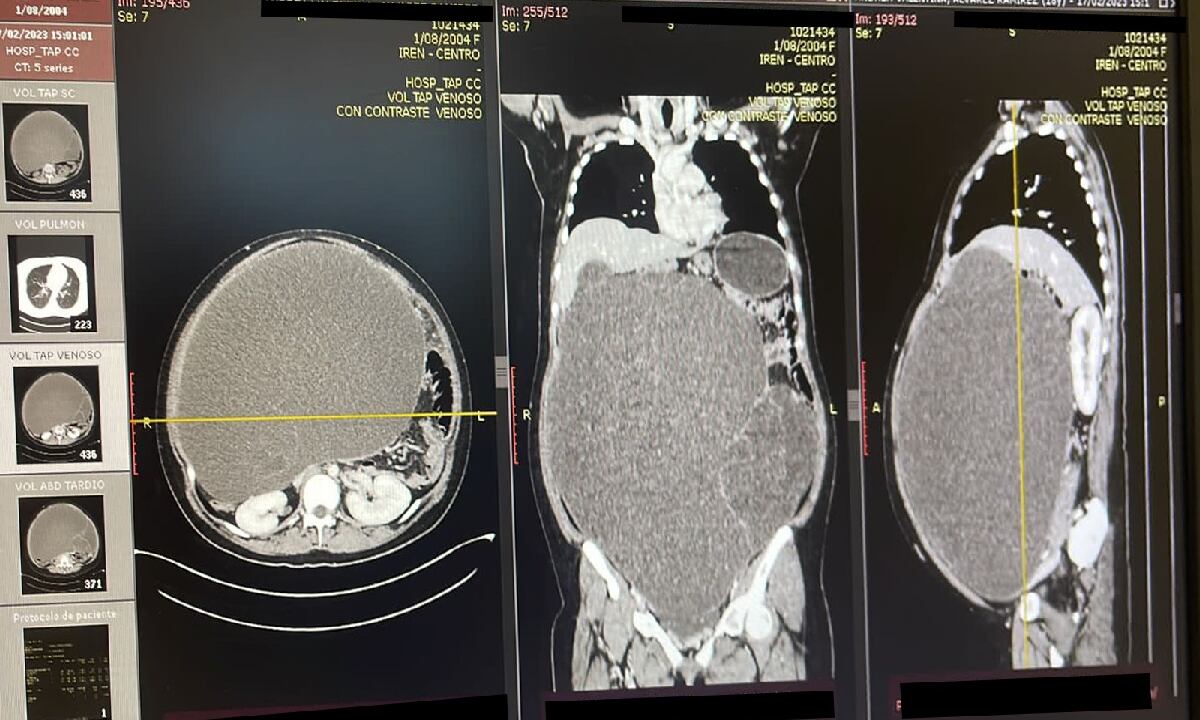

En medio de los exámenes médicos, los especialistas pudieron constatar que se trataba de la presencia de un abultado tumor que equivaldría casi a un embarazo gemelar, por lo que tras la práctica de las muestras requeridas, procedieron a operar de emergencia.

De acuerdo con medios locales que recogen la historia revelada por el Ministerio de Salud de ese país, el tumor llegó a pesar cerca de 20 kilogramos, lo que evidenció que este realmente estaba poniendo en peligro su vida, creciendo de forma paulatina ante los ojos de sus amigos y familiares que siempre lo asociaron con un caso de obesidad, sin sospechar que lo que yacía en ella era realmente un tumor.

En declaraciones recogidas por medios locales, se precisa que el encargado de la difícil cirugía fue el doctor Danilo Baltazar, subespecialista en ginecología oncológica, quien confirmó que la intervención fue exitosa, revelando que el gigantesco tumor se alojaba en la ‘cavidad abdominopélvica’, y precisando que este presentaba a su vez zonas quísticas y sólidas.

“Con éxito se extrajo la tumoración abdomino pélvica gigante con áreas quísticas y sólidas; y se envió a estudios patológicos”, refirió el médico Danilo Baltazar, subespecialista en ginecología oncológica del IREN Centro. pic.twitter.com/6mxqlyLoXO